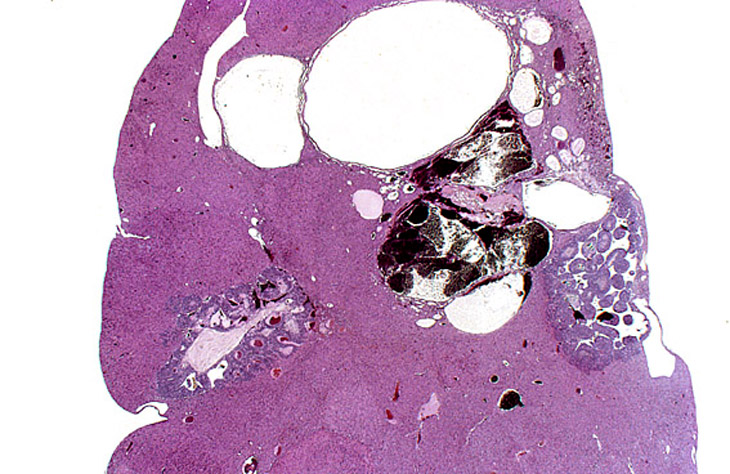

Hepatoblastomas and biliary cysts in the liver of an adult mouse.